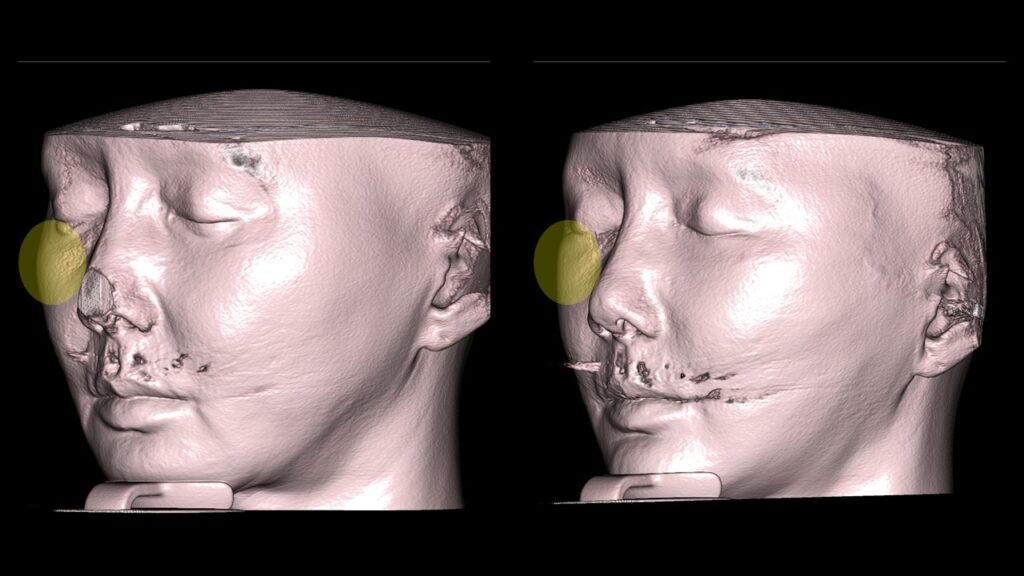

Zygoma (Cheekbone) Reduction: During a face lift, fat layers move upward and outward. To prevent the face from looking flat or wide, we reduce the side cheekbones.

4. Case Studies (3DCT & Medical Photos)

-

Case 2: (Zygoma + Chin Advancement + Face Lift + Brow Lift) Dramatic improvement in the side profile and double chin within just 1 month.